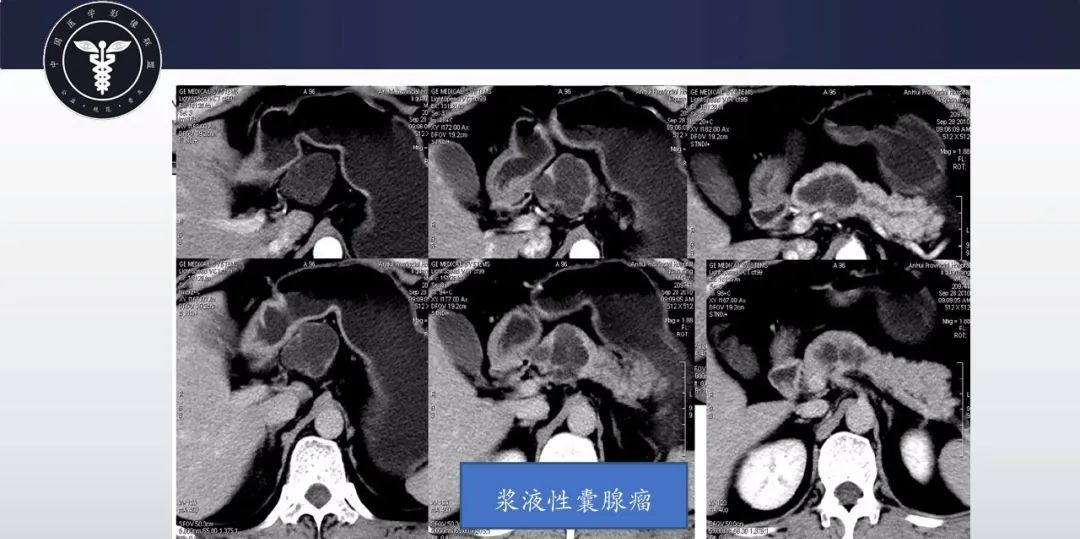

【病例】胰腺血管瘤1例CT及MR影像-3